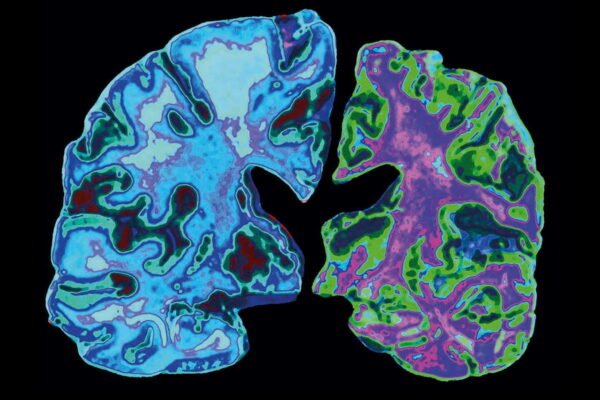

- Магнітно-резонансна томографія (МРТ) для виявлення змін у мозку.